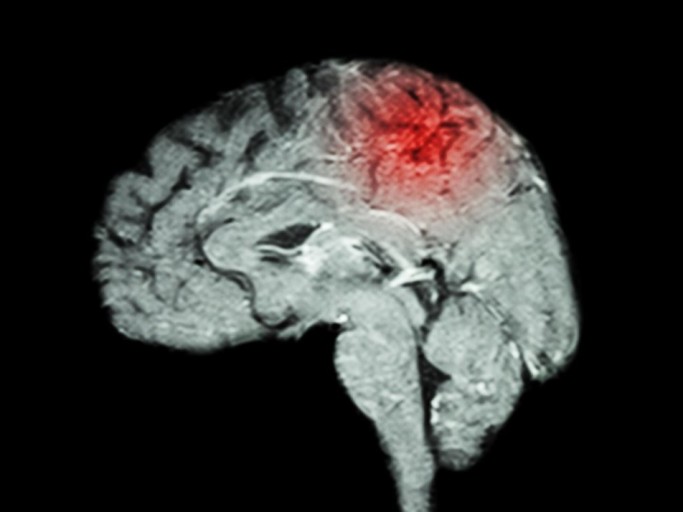

뇌졸중 전조증상 6. 갑작스럽고 참을 수 없는 두통

평소 두통이 없는 사람이 갑자기 벼락 맞은 듯한 극심한 두통을 겪는다면

뇌출혈(출혈성 뇌졸중)의 가능성이 높습니다.

특히 구토, 의식 저하, 경련이 동반된다면 즉시 응급실로 이동해야 합니다.7. 한쪽 감각 저하 또는 이상감각